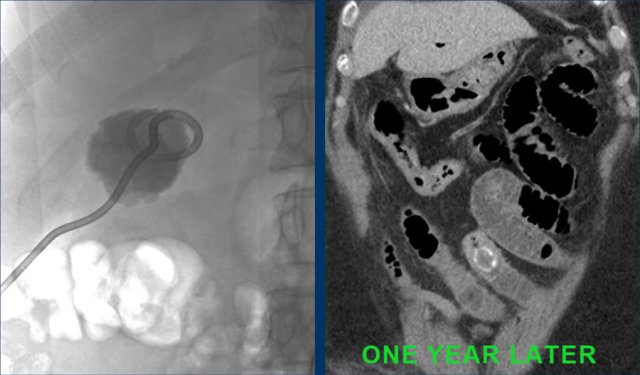

This is a patient with intermittent gastric retention and a low CRP.

Scroll through the images.

What are the findings?

A large stone got “stuck” in the fistulous tract from the deformed gallbladder to the duodenum.

Secondary wall thickening of the duodenum (arrowheads) and surrounding inflammatory and fibrous tissue, cause intermittent gastric retention with vomiting.

Images of an elderly lady, presenting with gastric retention and vomiting.

CRP was 55, but was documented to be 160 a few days earlier.

US shows a large stone in a gallbladder filled with debris-like material, and an irregular wall.

The stomach is dilated and there is remarkable wall thickening of the duodenum (arrowheads) and surrounding inflammation (asterisk).

Gastroscopy was done for suspected malignancy, but biopsy only revealed inflammation.

Continue with the CT.

CT confirms the diagnosis of Bouveret syndrome.

Percutaneous gallbladder drainage relieved the symptoms of gastric retention.

One year later, the stone apparently managed to evacuate to the duodenal lumen, and she developed a classic gallstone-ileus as yet, which was operated successfully.